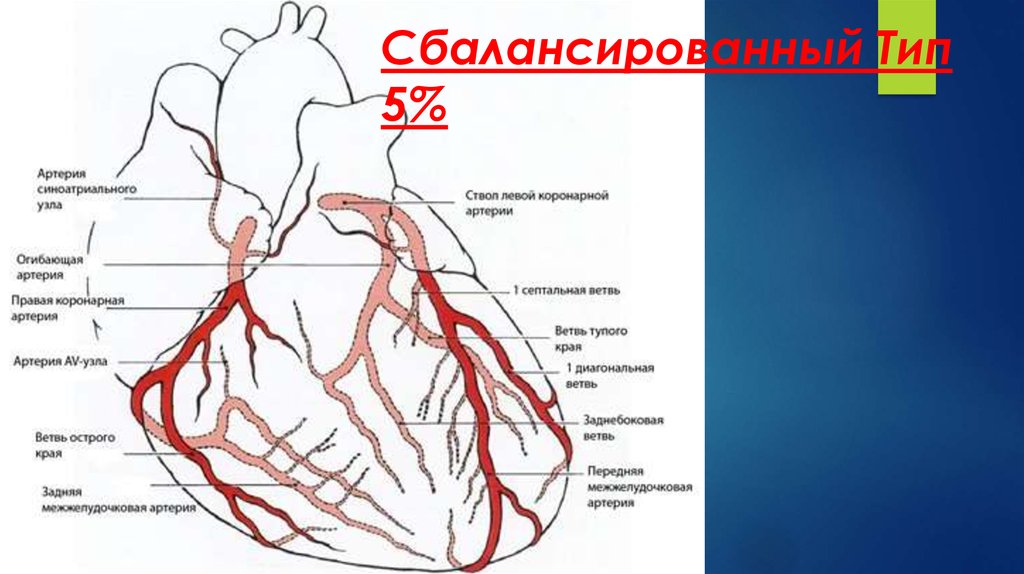

Анатомия коронарных артерий: КТ-изображения

Раздел: Снимки успеха